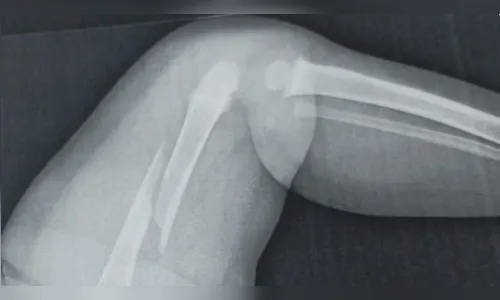

A Polícia Civil de Paiçandu, no noroeste do Paraná, investiga uma suspeita de agressão contra um bebê de um ano e cinco meses que está internado em Maringá com fratura no fêmur. Durante o atendimento hospitalar, a equipe médica constatou, além da lesão recente, uma fratura antiga no braço da criança, o que levantou a suspeita de maus-tratos.

A avó e o pai da criança afirmam suspeitar que o bebê sofria violência no ambiente em que vivia com a mãe e o padrasto. Com a confirmação da fratura antiga, um boletim de ocorrência foi registrado, e a família paterna solicitou a guarda provisória do menino, com a intenção de ingressar judicialmente com pedido de guarda definitiva.